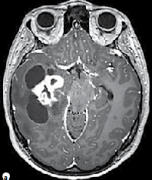

幼兒癡笑頻繁發(fā)作竟是下丘腦錯(cuò)構(gòu)瘤作祟,不開顱LITT技術(shù)究竟如何治療?

孩子的笑容天真無(wú)邪,活潑可愛的他們總能為家人帶來(lái)歡樂,然而當(dāng)孩子出現(xiàn)笑容無(wú)法控制,莫名頻繁發(fā)笑、怪笑、并且伴隨面部抽搐的情況,那就要小心了,也許并不是他們淘氣或者...

下丘腦錯(cuò)構(gòu)瘤嚴(yán)重嗎?切除之后還會(huì)癲癇發(fā)作嗎?

下丘腦錯(cuò)構(gòu)瘤嚴(yán)重嗎?下丘腦錯(cuò)構(gòu)瘤(HH)是一種先天性的發(fā)育畸形,其特征通常為多方位性的癲癇發(fā)作...